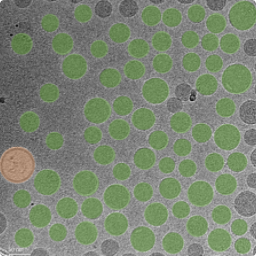

Particle Extraction and Size Distribution Statistics Based on Deep Learning

Thermo Science Amira is used to perform deep learning-based image segmentation on the cryo-EM images collected. After segmentation, the area of each particle is calculated by determining the number of pixels it occupies, which is then converted into the equivalent diameter, yielding the size distribution statistics. Additionally, the Length-to-Width Ratio (LWR) and surface rugosity of the particles can be calculated. For this type of analysis, we typically collect approximately 30 cryo-EM images and analyze a sample size of around 2,000 particles.

Size Distribution Statistics of Drug Delivery Systems